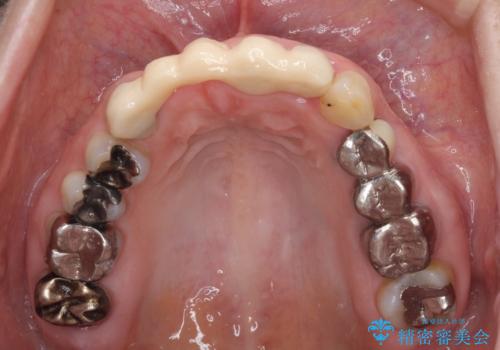

- 前歯のブリッジ治療中に装着していた仮歯が、あまりにも不自然で気になるとのことで来院された患者様です。

早急に仮歯をきれいなものに付け替え、オールセラミックブリッジにより補綴することとしました。

仮歯に置き換えた時点で見た目が大きく改善され、人目を気にすることがなくなりました。

オールセラミッククラウンは、本物の歯のような外観となり、患者様には大変満足していただけました。